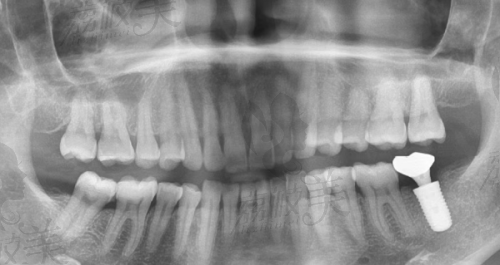

—— 即刻种植:患者“今天缺牙,明天就能大笑”,他用数据说话,让种牙从“等上几个月”变成“一气呵成”。

—— 微痛微创种植牙:张院长始终致力于减轻患者的手术恐惧,术中疼痛处理堪比剥葡萄皮,手术轻柔不言之中。

—— 上颌窦提升术及复杂骨增量:难度大,风险高,但这是他的“拿手好戏”;他曾在国内外会议上发表种植并发处理实例,收获大批同行点赞。

张俊伟医生不仅会“种牙”,更擅长“算牙”。他积极推广数字化种植技术,将传统经验与高端影像技术融合,种植过程效率高且精细,真正做到“种得稳、种得久、种得美”。他还是“技耗分离”理念的倡导者,强调医生技术和种植系统的各司其职,这不仅给患者带来合理的费用结构,也提高了整体治疗质量。